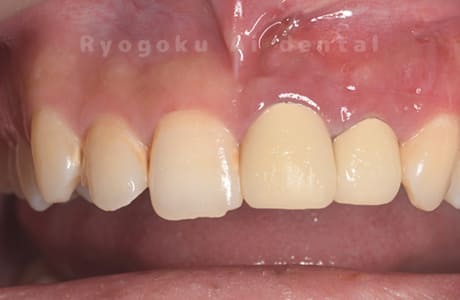

他院で抜歯と判断され、インプラント治療を提案された患者様です。被せ物を外さずに、歯の根尖部に外科的にアプローチし、病気の部分を除去しました。

<リスク・副作用>

外科手術のため、術後に出血、痛みや腫れ、違和感を伴います。口腔内の状態によっては適応できないことがあります。歯根端切除で治らなければ抜歯を検討しなくていけない場合もあります。